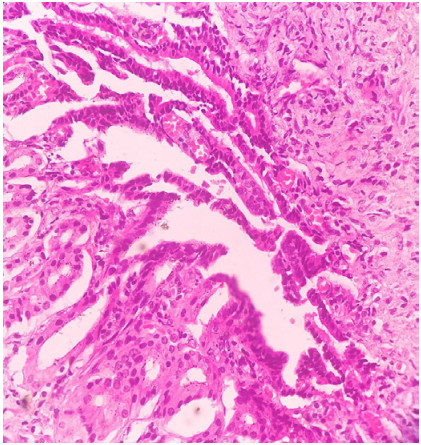

Abstract: Gallbladder tumors are the fifth most common cancers of the gastrointestinal tract with poor prognosis and low survival. The most common type is adenocarcinoma of which the clear cell type is an unusual histologic variant with alpha-fetoprotein (AFP)-producing gallbladder carcinoma, reported extremely rarely, which makes the index case an uncommon entity. AFP secretion by gallbladder carcinomas may occur given the similar embryological origin of liver and gallbladder. Herein we report a case of an incidental carcinoma of the gallbladder in a 60-year-old woman with an elevated serum AFP concentration at presentation, who underwent cholecystectomy for cholelithiasis and was rendered the diagnosis of AFP-producing clear cell carcinoma of the gallbladder through histopathology and immunohistochemistry. Her postoperative laboratory tests showed a decline in AFP levels to normal respectively. The clinical and pathologic importance of AFP production by clear-cell adenocarcinoma of the gallbladder (CCG) has thus far remained completely obscure. However, we must recognize the entity of this tumor because accurate and early diagnosis of CCG is imperative to avoid misdiagnosis as possible secondary metastasis and consequent delay in appropriate surgical intervention. Relevant medical history of a patient, various imaging studies, foci of classical adenocarcinoma within the tumor, and an efficient immunohistochemical panel can be informative and assist in arriving at an accurate diagnosis.